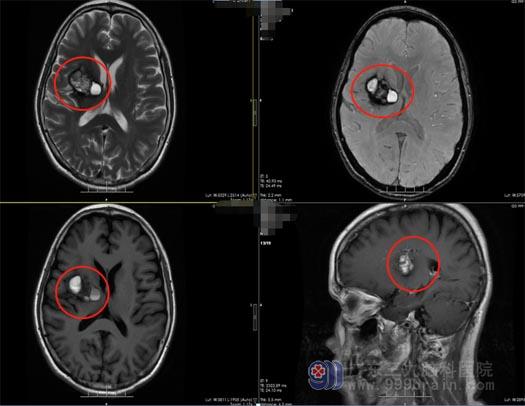

接诊的是神经外五科的王国良主任。经过详细询问病史及发病症状,王国良认为陈阿姨的头痛不是工作忙碌、休息不规律的原因,很可能是脑子长了肿瘤,头颅磁共振检查结果证实了王国良的判断,陈阿姨的脑子里确实有肿瘤,而且体积鸡蛋样大小,已经对周围神经产生了压迫,肿瘤侵犯了右侧基底节和丘脑。丘脑部位的肿瘤体积增大到一定的程度就会对周围的脑组织、血管、神经造成严重的压迫,容易导致偏瘫或肢体感觉障碍,还有可能出现消化道出血,诱发高热,出现生命体征紊乱。

王国良分析:“肿瘤不仅波及范围大,而且周围有很多重要的血管、神经和脑组织,手术中分离肿瘤时需要保护好血管和神经,避免大出血和副损伤,所以手术难度非常大。”经过反复讨论后,最终确定为陈阿姨实施“右侧基底节-丘脑-放射冠区病变切除术”。术中在高清显微镜辅助下,先仔细分离血管,切除部分肿瘤,再磨开视神经管,一点一点地将肿瘤从神经上剥离下来。经过5小时的奋战,最终肿瘤被完全摘除,神经与血管均无损伤,顺利切除肿瘤大小约6cm×5cm×5cm。术后不到两个星期,陈阿姨康复出院了,头疼头晕和手臂无力的症状都有所改善。